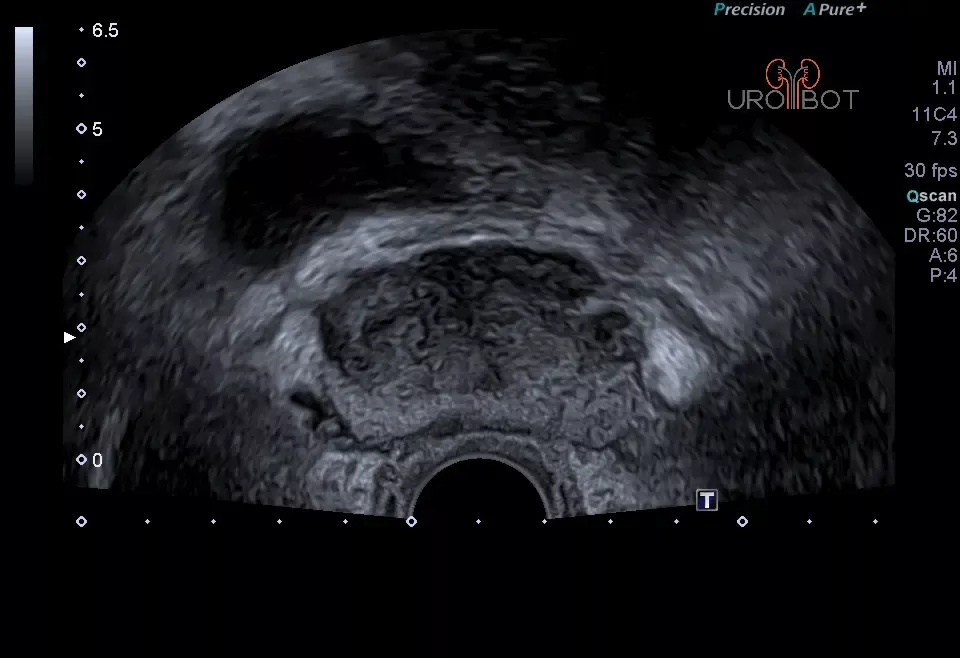

Prostata: Tumorbefund

Auf diesem Bild erkennt man die Prostata in zwei Ebenen mit Hilfe einer in den Enddarm eingeführten Ultraschallsonde.

Der ausgemessene Bereich, etwas dunkler dargestellt, entspricht einem größeren Tumorbefund in der Prostata.

Prostata: Tumorbefund

Auf diesem Bild erkennt man die Prostata in zwei Ebenen mit Hilfe einer in den Enddarm eingeführten Ultraschallsonde.

Der ausgemessene Bereich, etwas dunkler dargestellt, entspricht einem größeren Tumorbefund in der Prostata.

Prostata: Tumorbefund

Auf diesem Bild erkennt man die Prostata in zwei Ebenen mit Hilfe einer in den Enddarm eingeführten Ultraschallsonde.

Der ausgemessene Bereich, etwas dunkler dargestellt, entspricht einem größeren Tumorbefund in der Prostata.